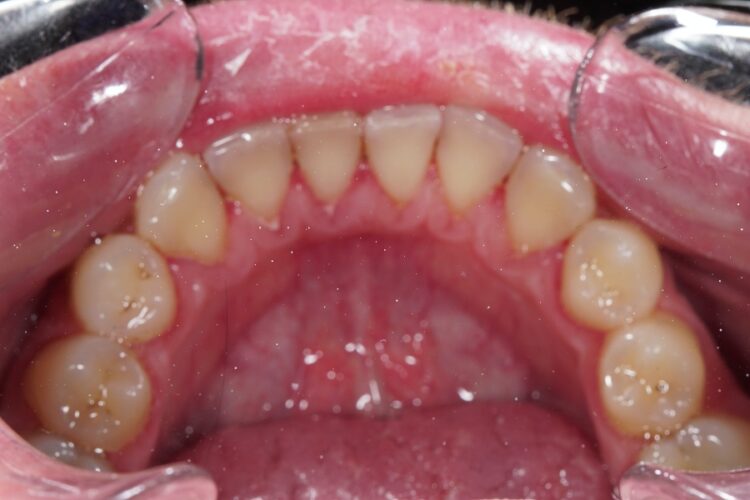

This involves removing dense pigmented plaque using a special PROPHYflex tip (or Air flow machine with a similar principle) that sprays a fine, calcium-containing powder called KaVo Prophypearls mixed with water onto the surface of the teeth under low pressure. This restores the natural color of the teeth, making them half or a full tone lighter, depending on the amount of plaque initially present.

Teeth cleaning according to the PROPHYflex technology is a continuation of the first stage of the procedure. A fine-dispersed composition based on calcium, water, and air (patented by Kavo) is delivered through the nozzle, which polishes the enamel and removes pigmented plaque in hard-to-reach areas.

Calcined round-shaped granules under air pressure contact the surface of the teeth, resulting in the elimination of roughness and the formation of a homogeneous smooth surface. As a result of using two different devices for removing calculus, dense pigmented and soft plaque, a lightening of the tooth enamel (by approximately one to two shades) is observed, although professional cleaning and teeth whitening are fundamentally different procedures.

Polishing after professional teeth cleaning is necessary to create a smooth enamel surface that prevents the attachment of microorganisms and, accordingly, the formation of calculus and foci of caries.